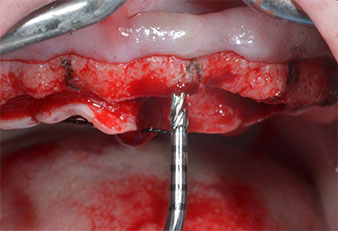

Implantatmotor (Implantmed)

Abb. 5: Der abschließende Durchmesser wird mit den Instrumenten Piezomed I3A/I3P erreicht. Die Implantatlager für die 10-mm-Implantate an Position 11 und 21 werden mit einem Implantatmotor (Implantmed) mit einem 3,5-mm-Spiralbohrer fertiggestellt.

Wegen des relativ harten Knochens (D2) an den Positionen 11 und 21 wurden die 10 mm langen Implantatlager in diesem Bereich abschließend mit einem 4-mm-Spiralbohrer, dem chirurgischen Winkelstück WS-75 L von W&H und dem W&H Implantmed Implantologiemotor in Verbindung mit dem optionalen W&H Osstell ISQ module präpariert. Im Gegensatz dazu wurde der weiche Knochen der Implantatlager im Seitenzahnbereich mit dem Piezomed I3P auf den abschließenden Durchmesser von 3 mm erweitert. Die Implantate wurden dann transgingival eingesetzt, die Einheildauer betrug drei Monate (Abb. 6-10). Die vorhandene Prothese wurde auf vier provisorischen Implantaten abgestützt (Abb. 8).